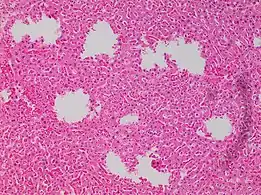

'Formalin pigment artifacts Air bubble entrapment artifact in a shoulder joint biopsy

Air bubble entrapment artifact in a shoulder joint biopsy Staining artifacts by residual wax, resulting in pale areas where cellular structures are not discernible.

Staining artifacts by residual wax, resulting in pale areas where cellular structures are not discernible..jpg.webp) A separation artifact in top image makes the tumor look incompletely excised, but the next microtomy level (bottom image) shows a surgical margin of connective tissue.